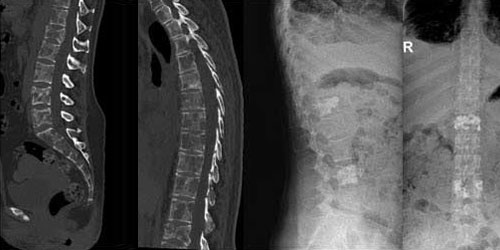

Omurga metastazı, kanserin ilk olarak iç organlarda gelişip daha sonra omurga kemiklerine yayılması sonucu oluşan bir durumdur. Çoğunlukla kan yoluyla sıçrayan bu tür metastaz, hastalarda sırt ve bel ağrısı gibi şikayetlerle kendini gösterir. Erken teşhis ve uygun tedavi yöntemleri, hastaların yaşam kalitesini artırmada kritik bir rol oynar.

Tedavide başarıyı artıran en önemli etkenlerden biri ameliyat öncesi iyi bir hazırlık ve cerrahi planlama yapmaktır. Her şeyden önce tanı doğru konmalı. Bunun için hasta iyi dinlenip, detaylı muayene edildikten sonra tetkikleri dikkatli incelenmelidir.

Her ameliyatın olduğu gibi kemik ve yumuşak doku tümör ameliyatlarının da riskleri vardır. Bu riskleri genel ve yapılan ameliyata özgü olmak üzere kabaca iki başlık halinde gruplandırabiliriz. Öncelikle anestezi ile ilgili risklerin anestezi uzmanı tarafından (...)

Ameliyat sonrası takip ve kontrol hastanın ameliyat masasında uyanması ile başlar. Özellikle damar ve veya siniri ilgilendiren ameliyatlarda hasta ameliyat masasından alınmadan ekstremitenin dolaşımı ve ilgili sinirin fonksiyonu kontrol edilir.